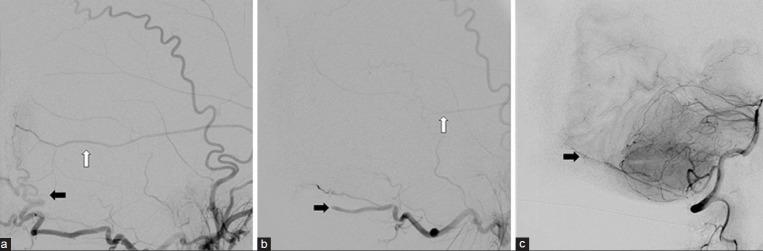

A 48-year-old male presented after 3 days of worsening headaches and blurry vision. Preoperative imaging demonstrated an 11 × 5-cm extra-axial mass that avidly enhanced with gadolinium in the region of the torcula. Angiography demonstrated occlusion of the involved portions of the superior sagittal sinus, torcula, and proximal left transverse sinus. Cortical drainage occurred via the veins of Labbι and deep drainage via an occipital sinus. Using image-guided stereotaxy, a wide-excision scalp resection and craniectomy with sinus exploration was planned for complete tumor removal. Parasitized cortical veins were preserved. Occluded portions of the superior sagittal sinus and left transverse sinus were resected along with the invaded parts of the falx and tentorium. The walls of the straight sinus, torcula, and right transverse sinus were repaired primarily to facilitate deep drainage. A latissimus dorsi free flap was used to reconstruct the scalp defect. Routine follow-up magnetic resonance imaging (MRI) at 18 months demonstrated no evidence of recurrence or regrowth.

一名48岁男性在头痛和视力模糊加重3天后就诊。术前影像学检查显示一个11×5厘米的轴外肿块,在窦汇区域钆增强明显。血管造影显示上矢状窦、窦汇和左侧横窦近端受累部分闭塞。皮质引流通过Labbe静脉进行,深部引流通过枕窦进行。采用影像引导立体定向技术,计划进行广泛的头皮切除和颅骨切除术并探查窦,以完整切除肿瘤。保留寄生的皮质静脉。切除上矢状窦和左侧横窦的闭塞部分以及镰和小脑幕的受累部分。直接修复直窦、窦汇和右侧横窦的壁以促进深部引流。使用背阔肌游离皮瓣修复头皮缺损。18个月的常规随访磁共振成像(MRI)显示无复发或再生长迹象。